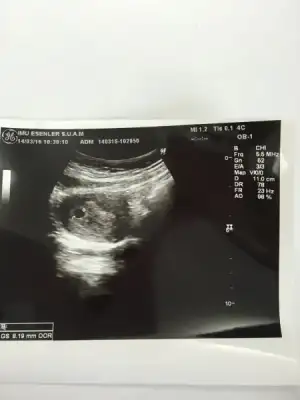

Canım ultrasondaki kağıtta kaç haftalık olduğun yazıyo? Ve kaç mm? Bende bugun gördüm çok şukur ama karından göremedi doktor alttan baktı ve ultrasona göre 4 hafta 6 günlük 0.88 cmBU DA KESEMİZ DOKTOR ÇOK GÜZEL DEDİ MAŞALLAH HERKES KIZIN OLCAK DİYO NORMALDE KIZ ÇOCUKLARINI PEK SEVİMLİ BULMAM NEDENSE BENİMDE GÖNLÜMDEN GEÇEN KIZ

benim de 4+6 da 0,87 ydi :) aynı gidiyor bebişler sanki sadece benim bugün 6+2 kalp atışımızı duymak için son 2 gün kaldı :)Canım ultrasondaki kağıtta kaç haftalık olduğun yazıyo? Ve kaç mm? Bende bugun gördüm çok şukur ama karından göremedi doktor alttan baktı ve ultrasona göre 4 hafta 6 günlük 0.88 cm![]()

Bana da doktor iki hafta sonra gel dedi kalp atısı için. Ozaman sen 6+4 de duyarsan bende duyarım inşaalllah. Cumartesıye denk gelıyor hem eşimle gitmiş olurumbenim de 4+6 da 0,87 ydi :) aynı gidiyor bebişler sanki sadece benim bugün 6+2 kalp atışımızı duymak için son 2 gün kaldı :)

CANIM EKTE FOTOSU SEN Bİ BAK İSTERSE BENDE 11.0 CM YAZIYO SANIRIMCanım ultrason kağıdının sğ altta yazıyor GS 0.88 CM yazıyor mesela bende